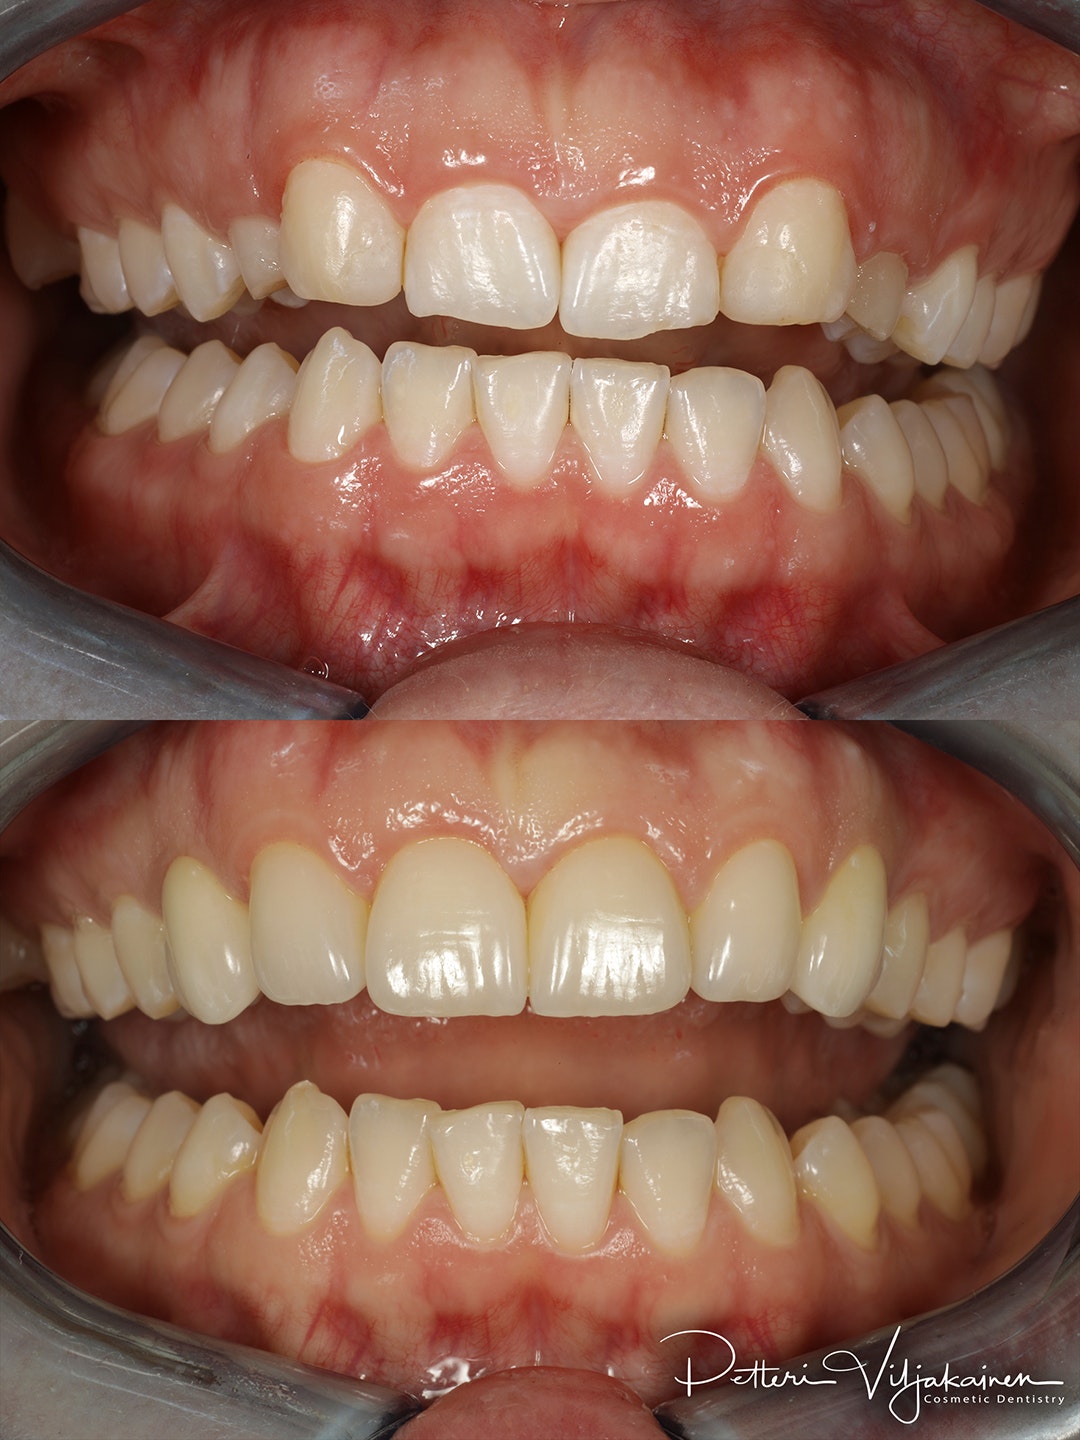

Keraamiset laminaatit neljässä yläetuhampaassa. Kulmahampaat korvattu implanttikruunuilla. Oikomista tehty ennen kuoria.

Oikomista tehty ennen kuoria.